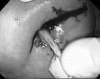

The management of enterocutaneous fistulas continues to be a challenging postoperative complication. Understanding the anatomy of the fistula optimizes its evaluation and management. Diagnostic radiology has always played an important role in this task. The use of plain radiography with contrasted studies and fistulograms is well documented in the earliest investigations of fistulas and they continue to be helpful techniques. The imaging techniques have evolved rapidly over the past 15 years with the introduction of cross-sectional imaging, ultrasound and endoscopy. The purpose of this chapter is to review both the diagnostic and therapeutic roles of fistulograms, small bowel follow-through, computed tomography, magnetic resonance imaging, ultrasound, and endoscopy in the setting of acquired enterocutaneous fistulas.